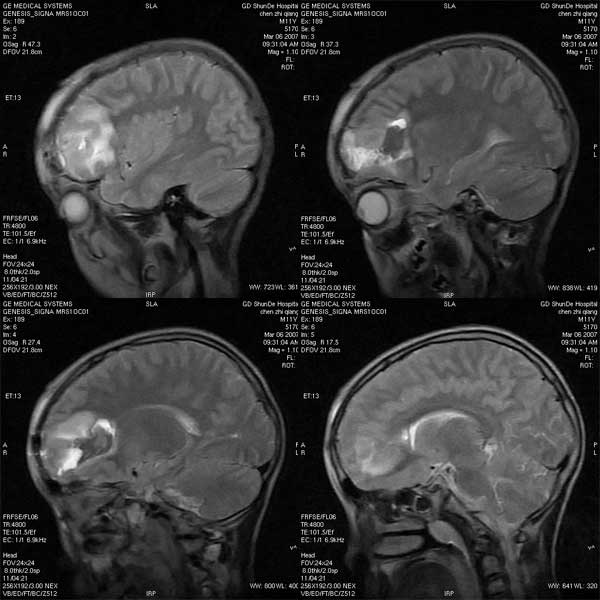

性别:m

年龄:11

病历摘要:右颞开放性颅脑损伤治疗后复查